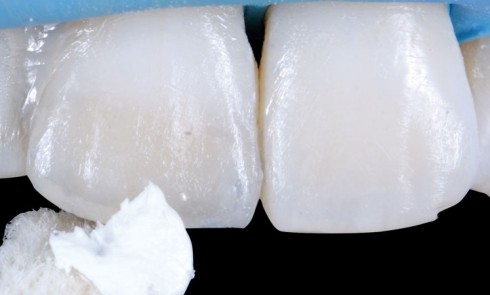

Article réservé à nos abonnés Intégration d’une restauration composite sur une incisive centrale

Les améliorations technologiques des matériaux comme le composite ont eu lieu en réponse à une demande esthétique croissante des patients....